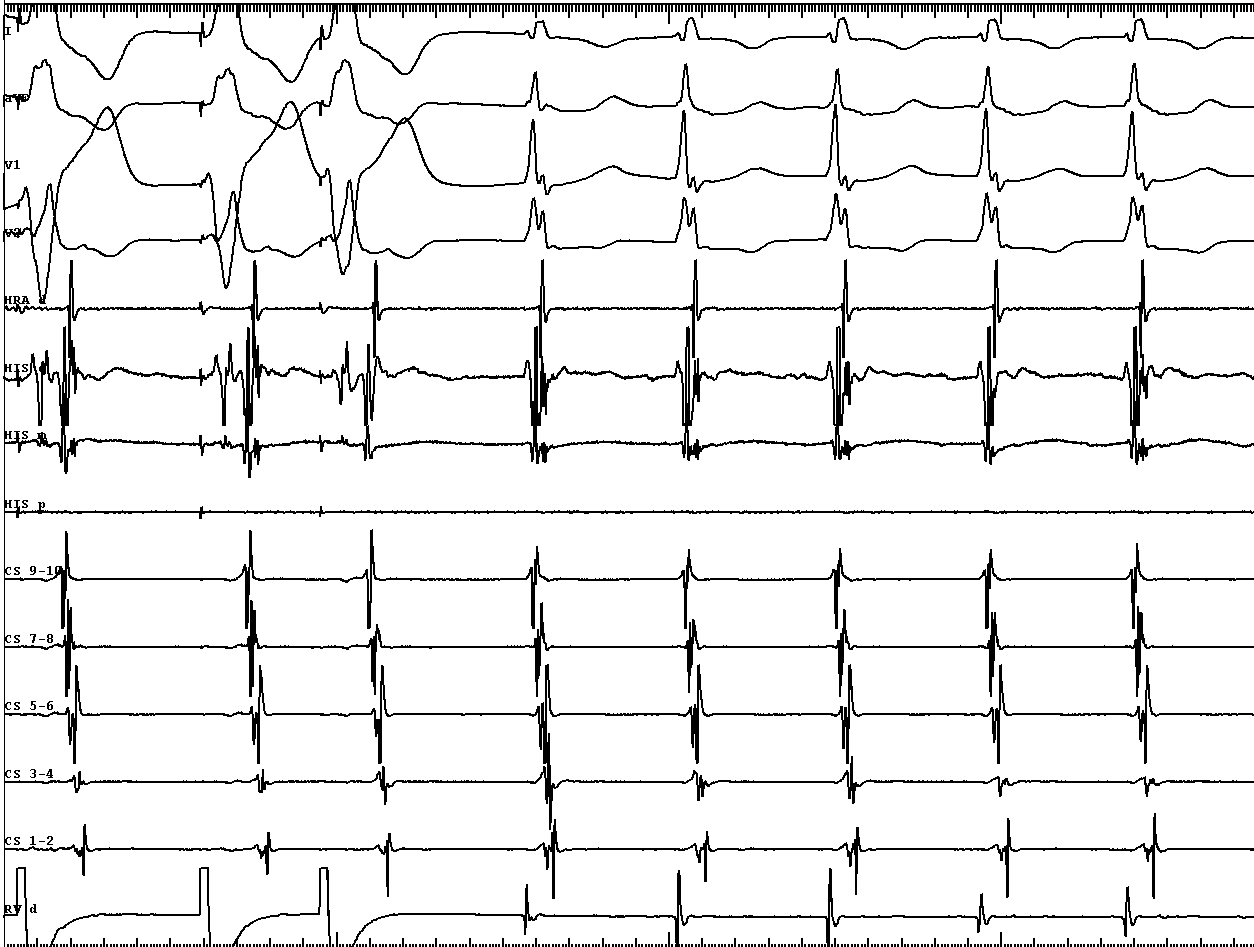

EP study - Sinus rhythm

sinus_post_HIS.jpg

Tachycardia induction

tachy_induction.jpg

tachy_1.jpg

• VA conduction with His after A - ? AP

tachy_2.jpg

• VA conduction with His after A - bystander His activation, ? AP

• VH block with VA conduction - further confirms bystander His